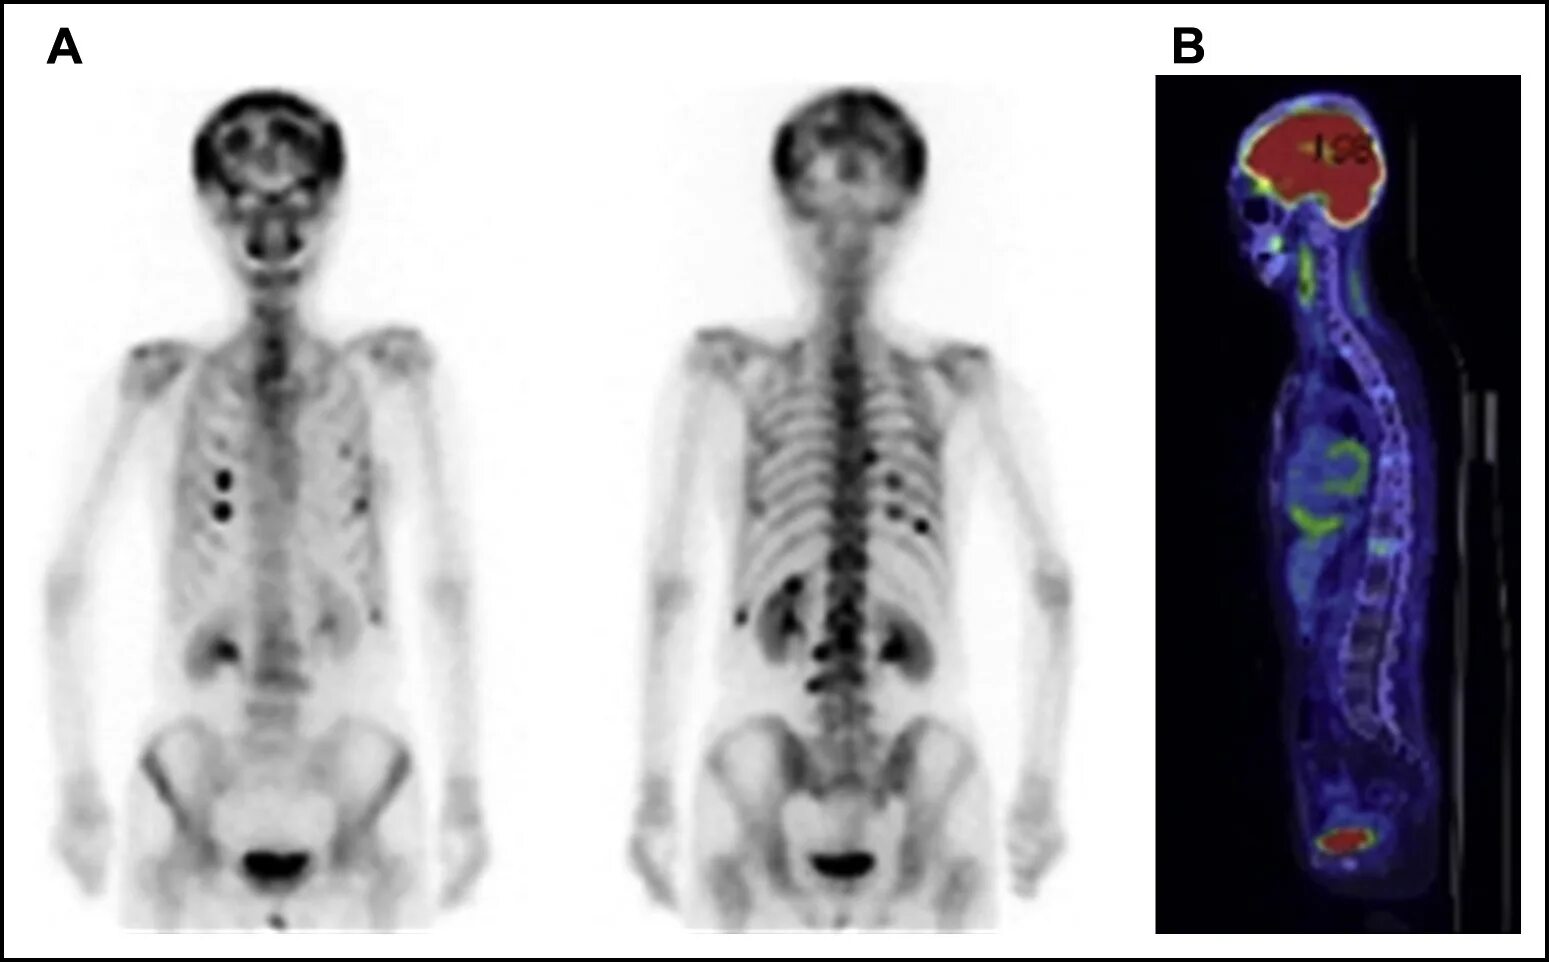

Метастазы скелета